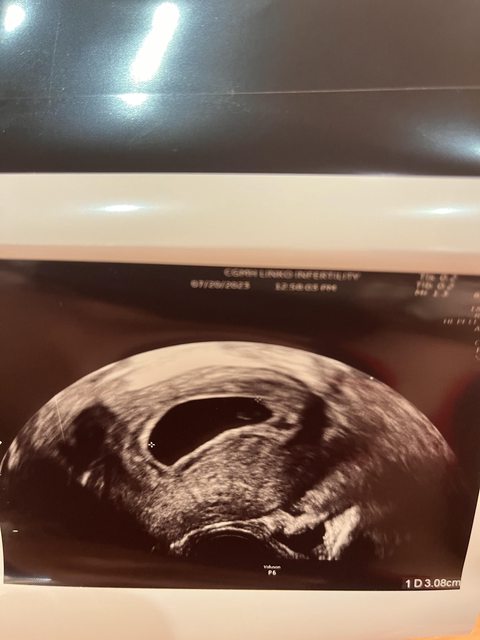

昨天8W4D回診,還是無心跳,但囊胚有持續變大,而且照出卵黃囊(如下圖)醫生是建議可 以等1週,但如果1周沒有的話可能就要處理掉。 https://i.imgur.com/Bvgf6K5.jpg